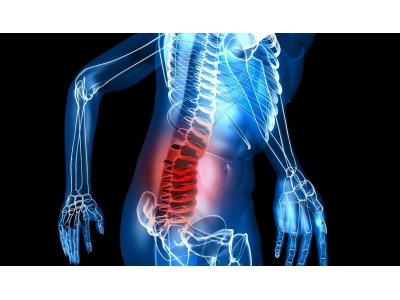

Estudio comparativo sobre la función y la electromiografía de superficie en pacientes con hernia de disco lumbar tratados con acupuntura y moxibustión.

Comparar las diferencias en la función clínica y la miodinia lumbar y abdominal en pacientes con hernia de disco lumbar tratados con moxibustión en Dazhui (GV 14) y Guanyuan (CV 4) y acupuntura.

La moxibustión en Dazhui (GV 14) y Guanyuan (CV 4) y la acupuntura convencional mejoran la función muscular, alivian la fatiga muscular, aumentan la capacidad de la fatiga muscular, fortalecen la estabilidad vertebral lumbar, liberan los síntomas subjetivos y mejoran el ADL. pero, los efectos de la moxibustión son ligeramente más bajos que los de la acupuntura.